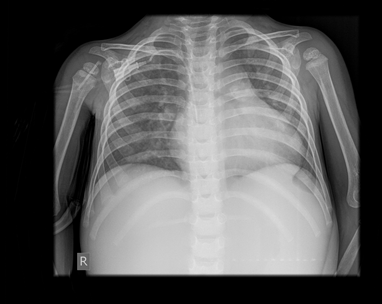

The ventricles are balanced. The patch placed on the defect in the perimembranous-outlet region in the interventricular septum was seen as echogenic, a left-to-right shunt from the 3mm residual defect at the upper end of the patch and a 38mmHg gradient between the two ventricles was detected large, lobulated echogenic and mobile mass was seen in the pulmonary valve. Measured 12-15mm in diameter. It was determined that it extended towards the right pulmonary artery with a thin pedicle and the length of the extension was 17mm. A 32mmHg gradient was measured at the valve level, and mild insufficiency was determined. There is degree 2 insufficiency of the tricuspid valve. Flow velocity was measured at 3.8m/s (58mmHg). RV pressure has been estimated at 60-65mmHg. The aortic valve has three cusps, with minimal regurgitation. There is mild (1st degree) regurgitation from the mitral valve. Thrombus/vegetation was not observed in other vessel cavities on tricuspid, mitral and aortic valves. Coronary artery outputs are normal. Left ventricular function is normal. RF about 65% here is no pericardial effusion (Figure 1 & 2).

Figure 1 Transthoracic echocardiogram: A parasternal, short-axis view shows a mobile mass consistent with vegetation adjacent to the pulmonary valve.